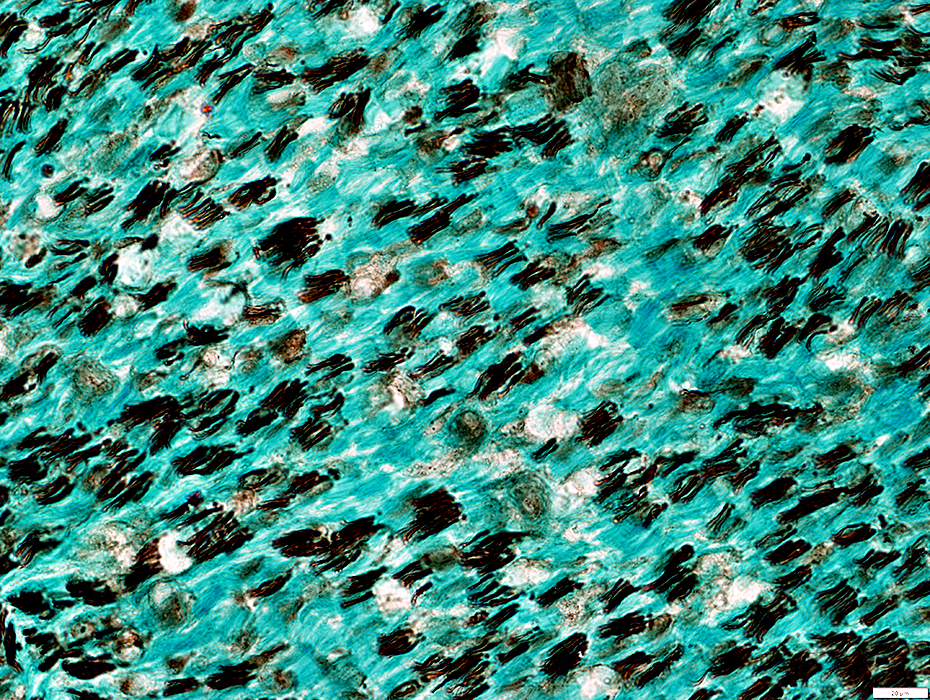

Gomori trichrome stain

Myelinated Axons

Reduced number

Damaged myelin (Loss of red color)